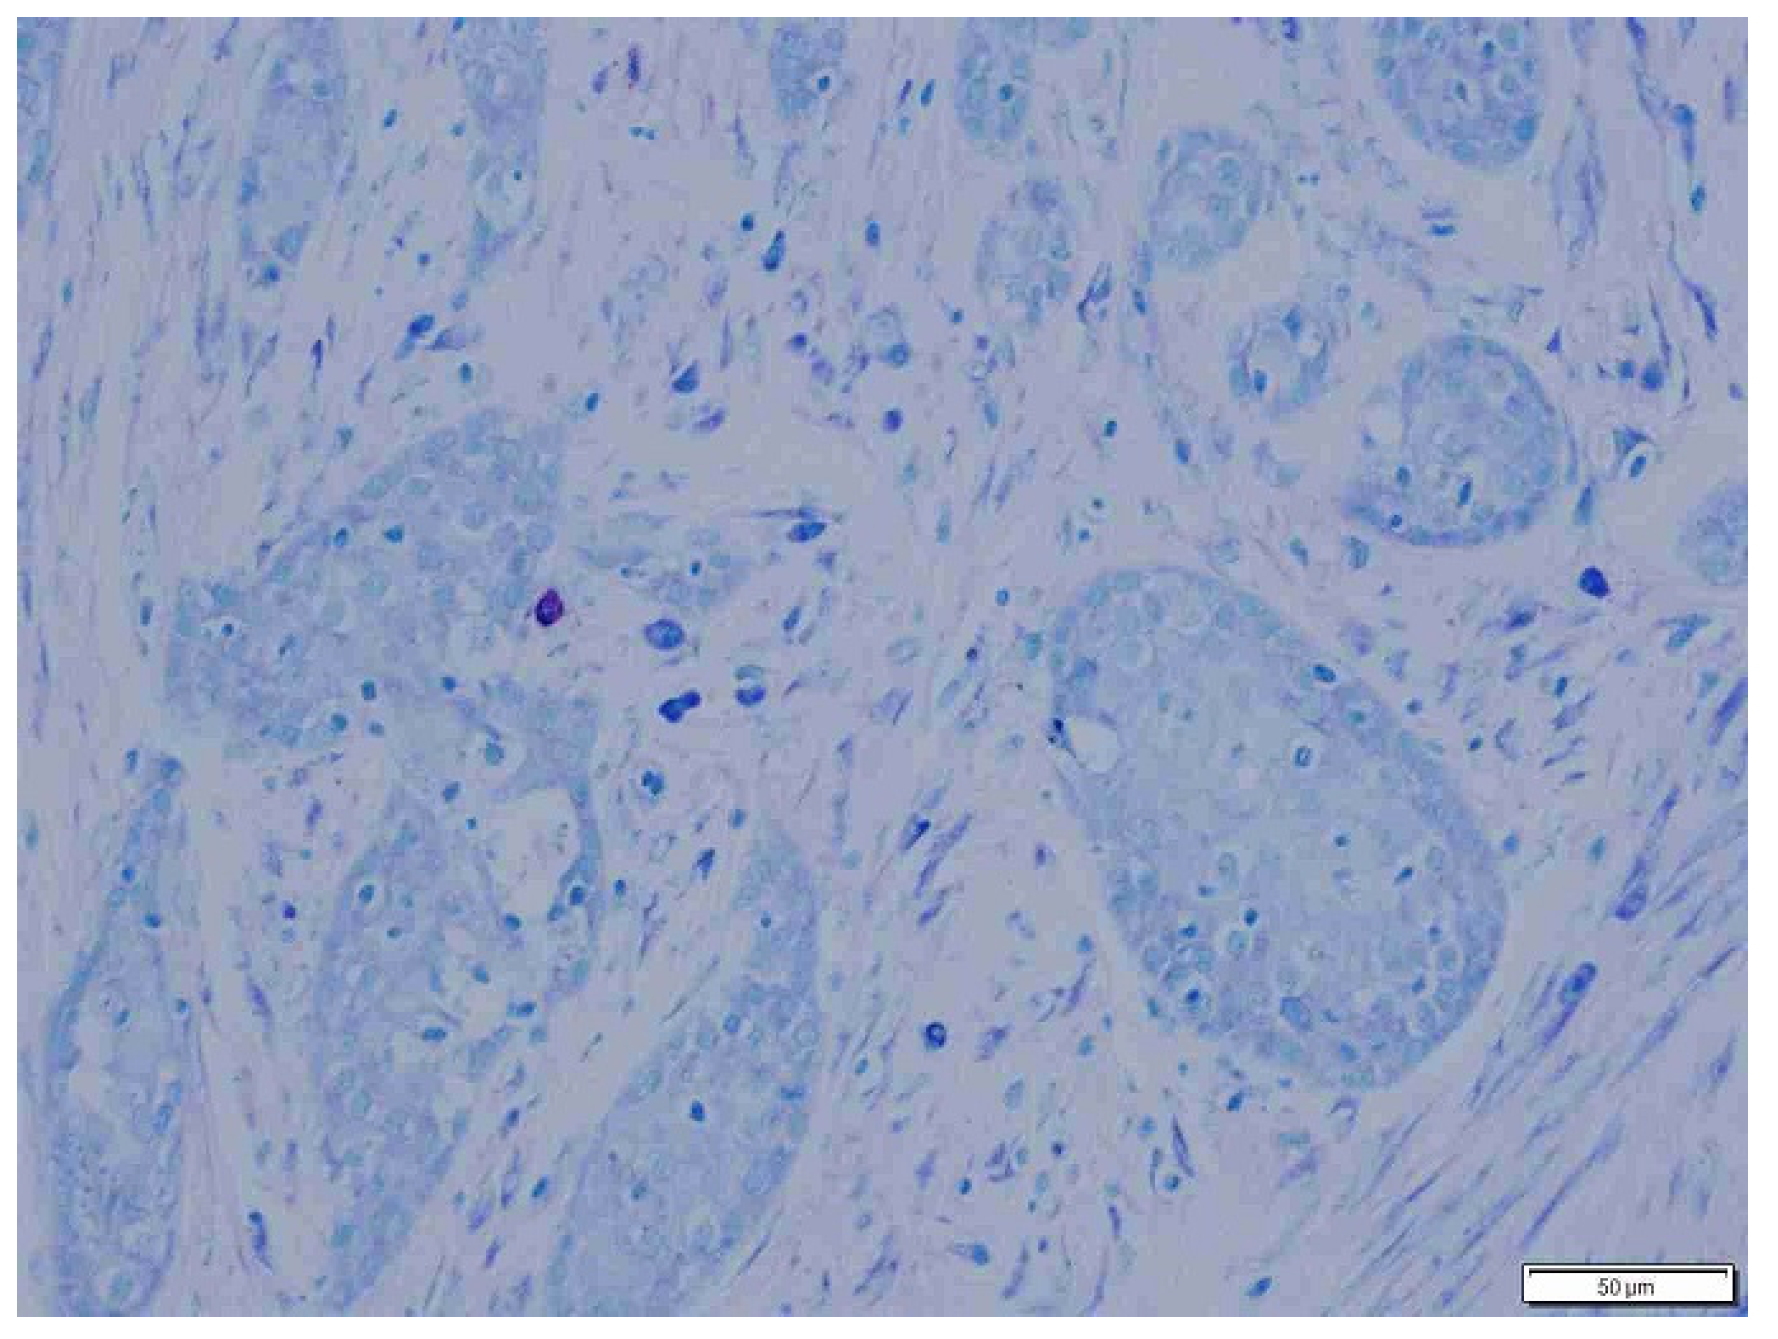

2.4. Histopathology

3. Results